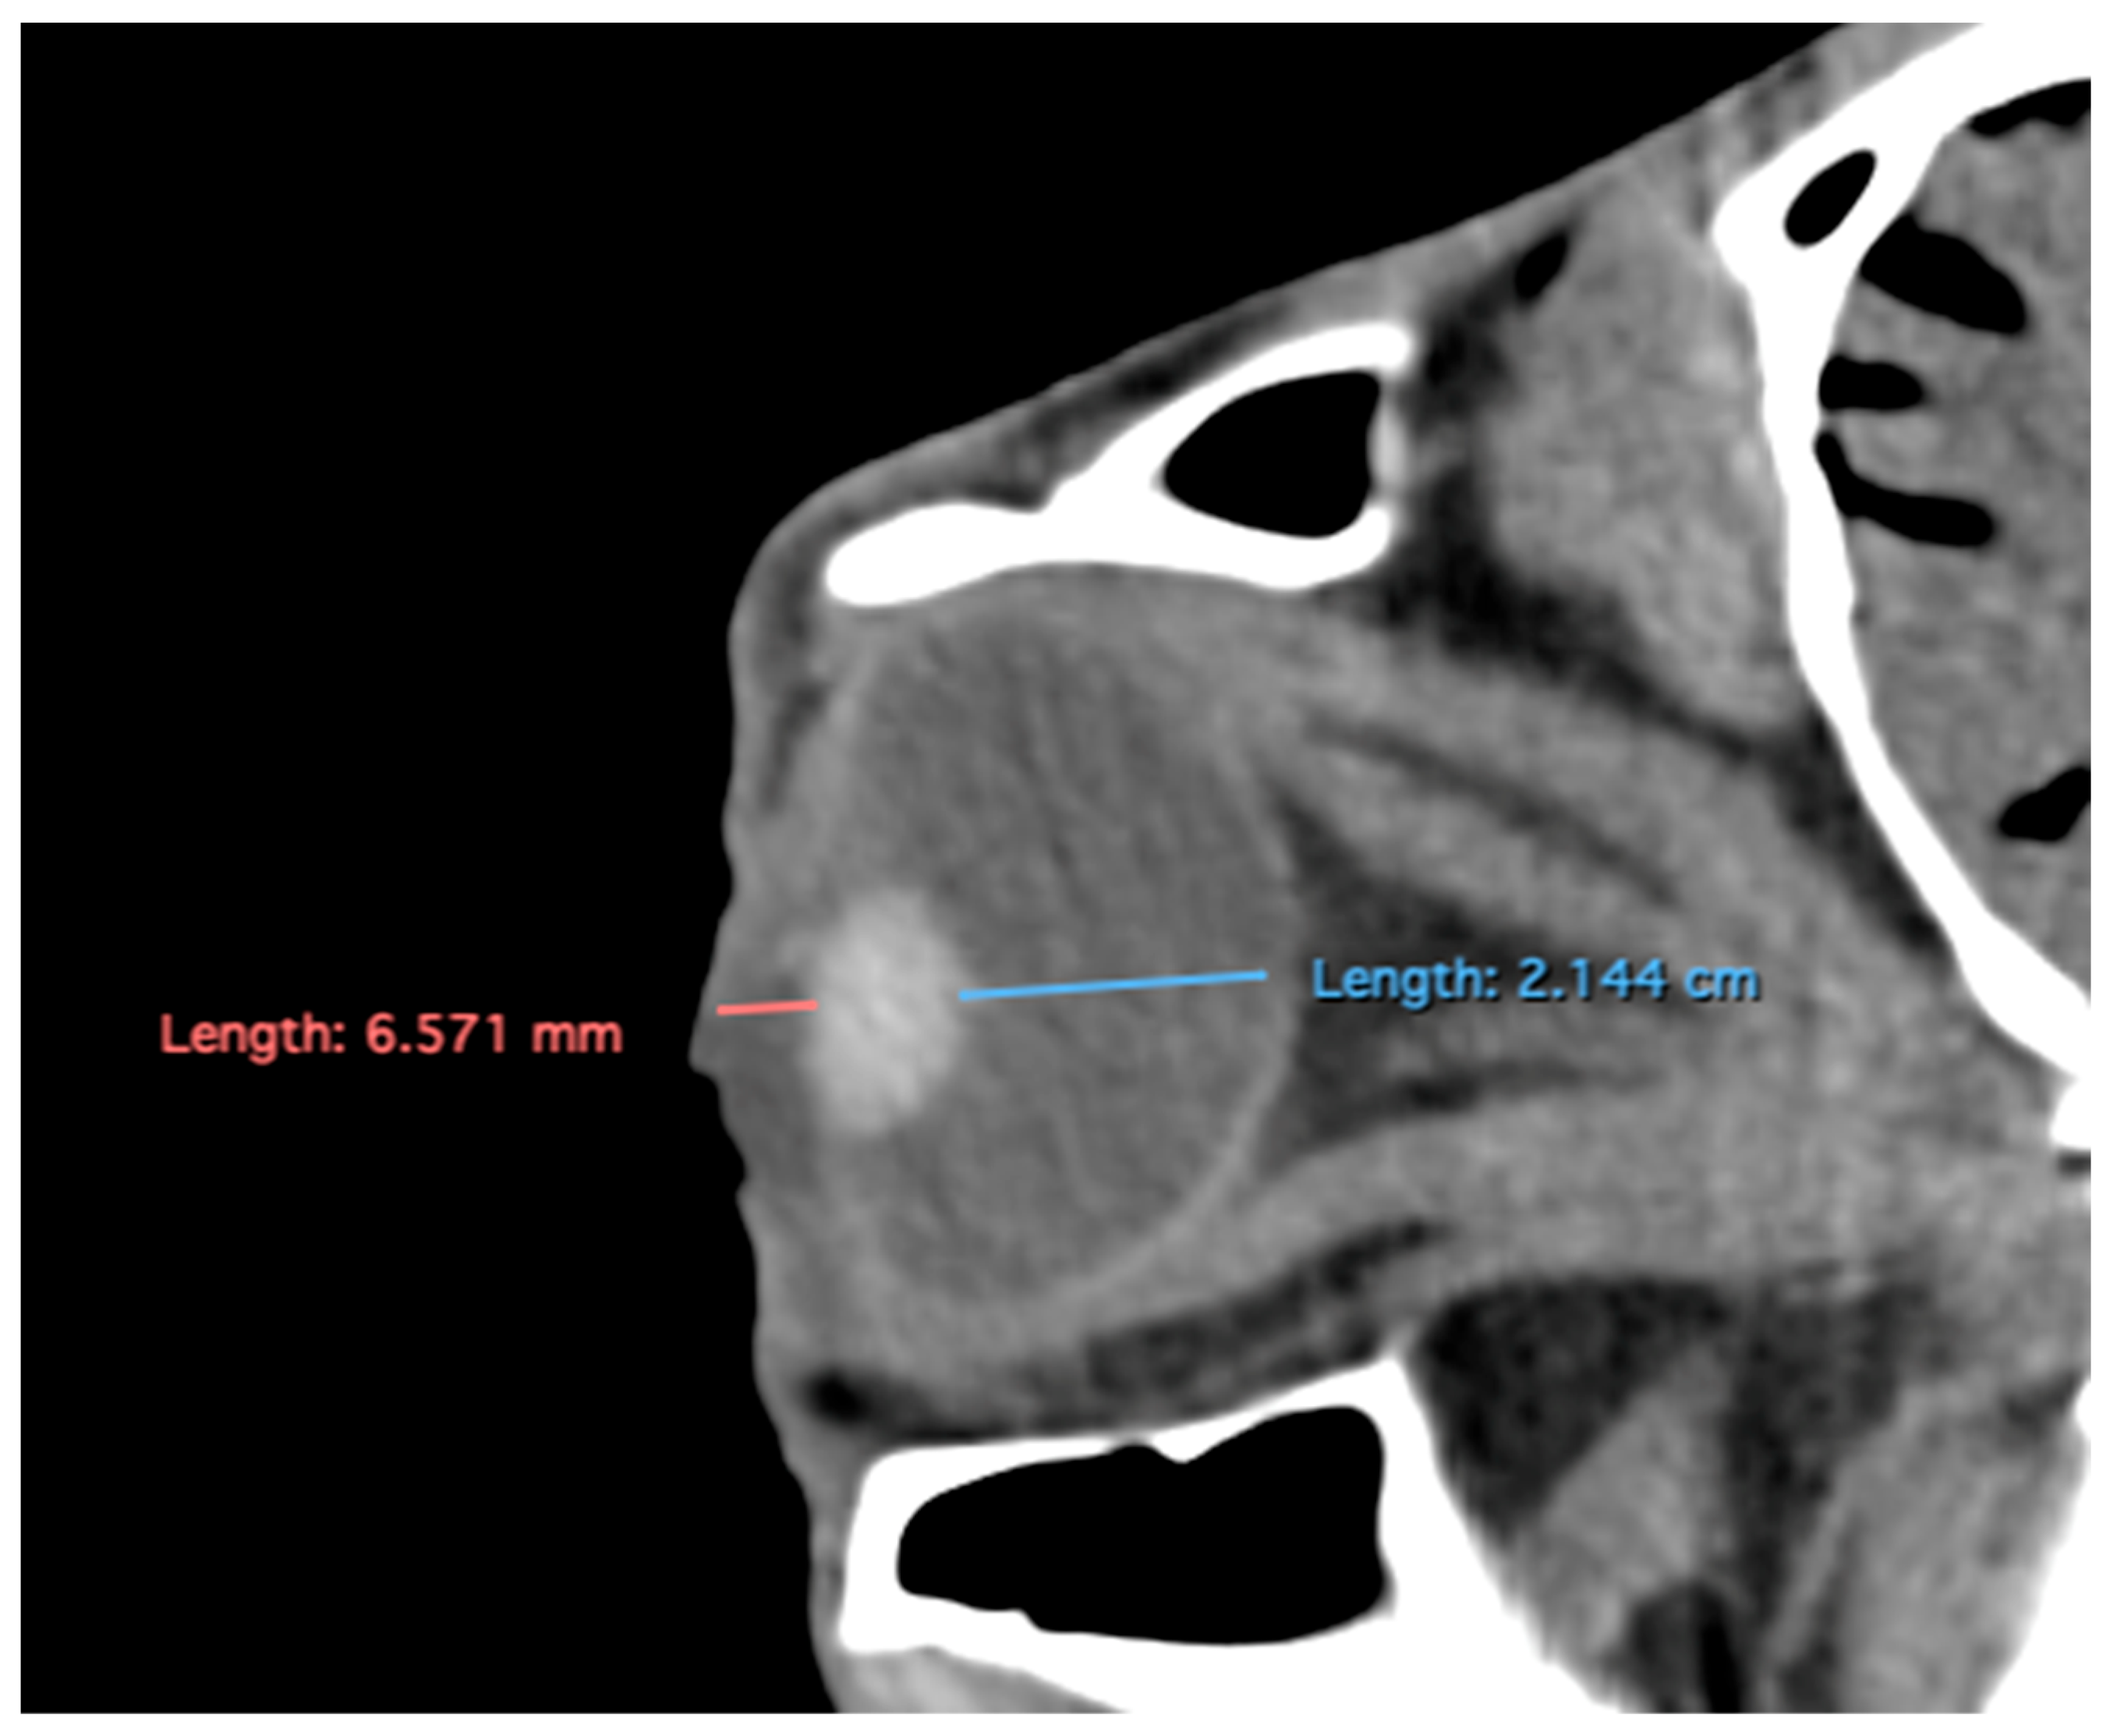

- Eyeball equatorial width and height: Maximal anterior–posterior distance (Figure 1A) and maximal lateromedial distance of the eyeball, measured perpendicular to the axial length (Figure 2B).

Figure 2. Dorsal multiplanar reconstruction (MPR) images showing (A) the maximal latero-medial distance of the lens and (B) the maximal latero-medial distance of the eyeball, measured perpendicular to the axial length, immediately caudal to the lens. - Orbital cavity height: Maximal dorsoventral distance of the orbital cavity at the level of the eyeball.

Table 1 provides summary statistics (mean, median, range, and standard deviation) for the internal ocular measurements of the left eye, right eye, and both eyes combined across all 20 horses. The average ocular measurements indicated that the eyeball height (5.19 ± 0.13 cm) was greater than its width (4.28 ± 0.12 cm), confirming the characteristic oval shape of the equine eye. The mean axial length was 5.09 ± 0.17 cm, consistent with previous descriptions of large-globe morphology in horses. The orbital cavity measured 5.27 ± 0.12 cm in height and 6.29 ± 0.14 cm in length. The anterior and posterior chambers had mean widths of 0.56 ± 0.07 cm and 2.26 ± 0.09 cm, respectively. The lens exhibited a mean height of 1.53 ± 0.06 cm, width of 1.23 ± 0.06 cm, and length of 1.63 ± 0.04 cm. These results collectively reflect the regular proportions and bilateral symmetry of the equine eyeball and its internal structures, as detailed in Table 1. The Mann–Whitney U test revealed no statistically significant differences in the measurements between the right and left eyes. Similarly, when all variables were considered collectively, the analysis confirmed the absence of significant differences between both eyes